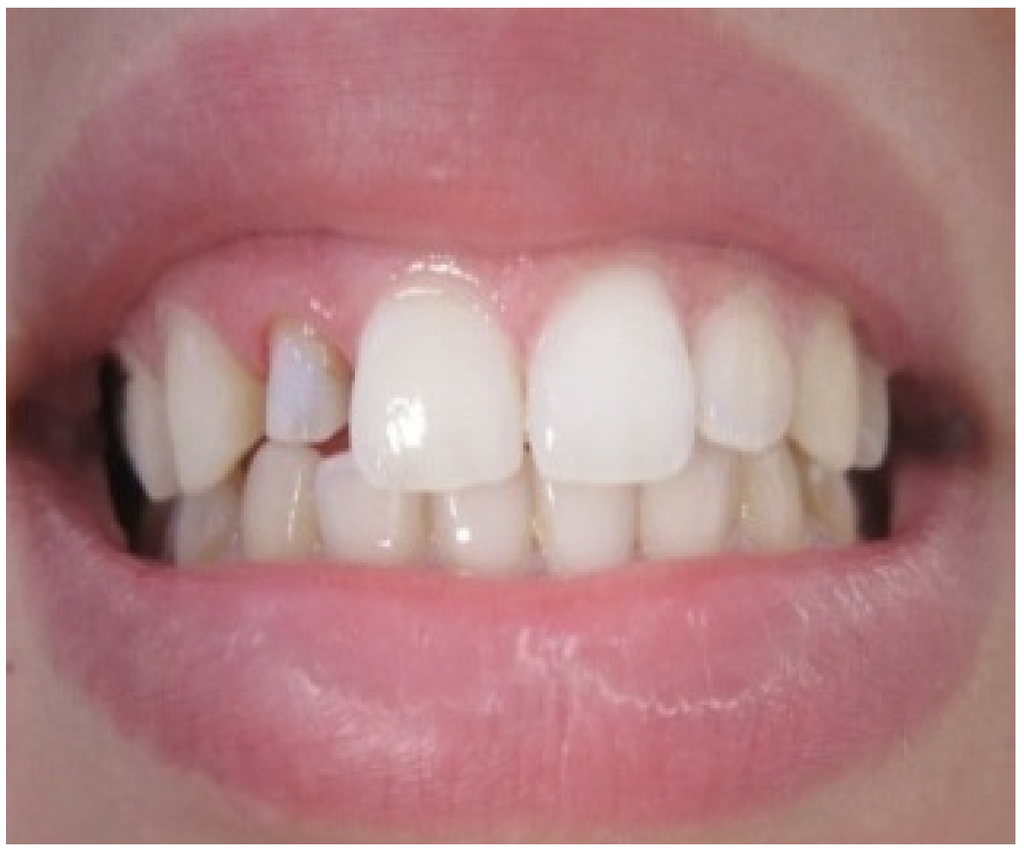

A 25-year-old dental student presented to the department of prosthetic dentistry with a chief complaint of poor aesthetics due to her imperfect metal ceramic single crown in the lateral incisor. She was bothered about the visible dark areas under the crown margins and requested an aesthetic rehabilitation. She also expressed her dissatisfaction with its color and shape. Intra oral examination showed dark gingival margins in the lateral incisor caused by metal frame (Figure 1). Soft tissues were evaluated as healthy with a wide band of attached gingiva in the maxillary region and a good oral hygiene.Visual assessment and Periodontal probing revealed a thick healthy gingival biotype with gingival thickness of 2 mm. and a sulcus depth of 2 mm. Bone sounding revealed a crest position in close relationship relative to anticipated post-surgical gingival margin level (2.5 mm). As the patient presents a thick periodontal biotype, this would significantly influence the post-operative procedure in favor of the esthetically desired outcome as this type is less prone to post-surgical recession.

Aesthetic assessment showed a squared teeth form, a size discrepancy and a non-symmetrical gingival architecture between the left and right lateral incisors (Figure 2). A slight asymmetry between the gingival margins of the right and left central incisors was noticeable. However, the patient did not express her dissatisfaction about it and refused any surgery on her sound teeth.

Gingival zenith was evaluated as non-aesthetic as it occupies a location that does not coincide with the long axis of the tooth.

Gingival display was evaluated as more than 4 mm on the side of the lateral incisor when smiling. Radiographic examination revealed an adequate root canal filing with no bone loss.

Figure 2. Gingival display due to the asymmetrical ZENITH.